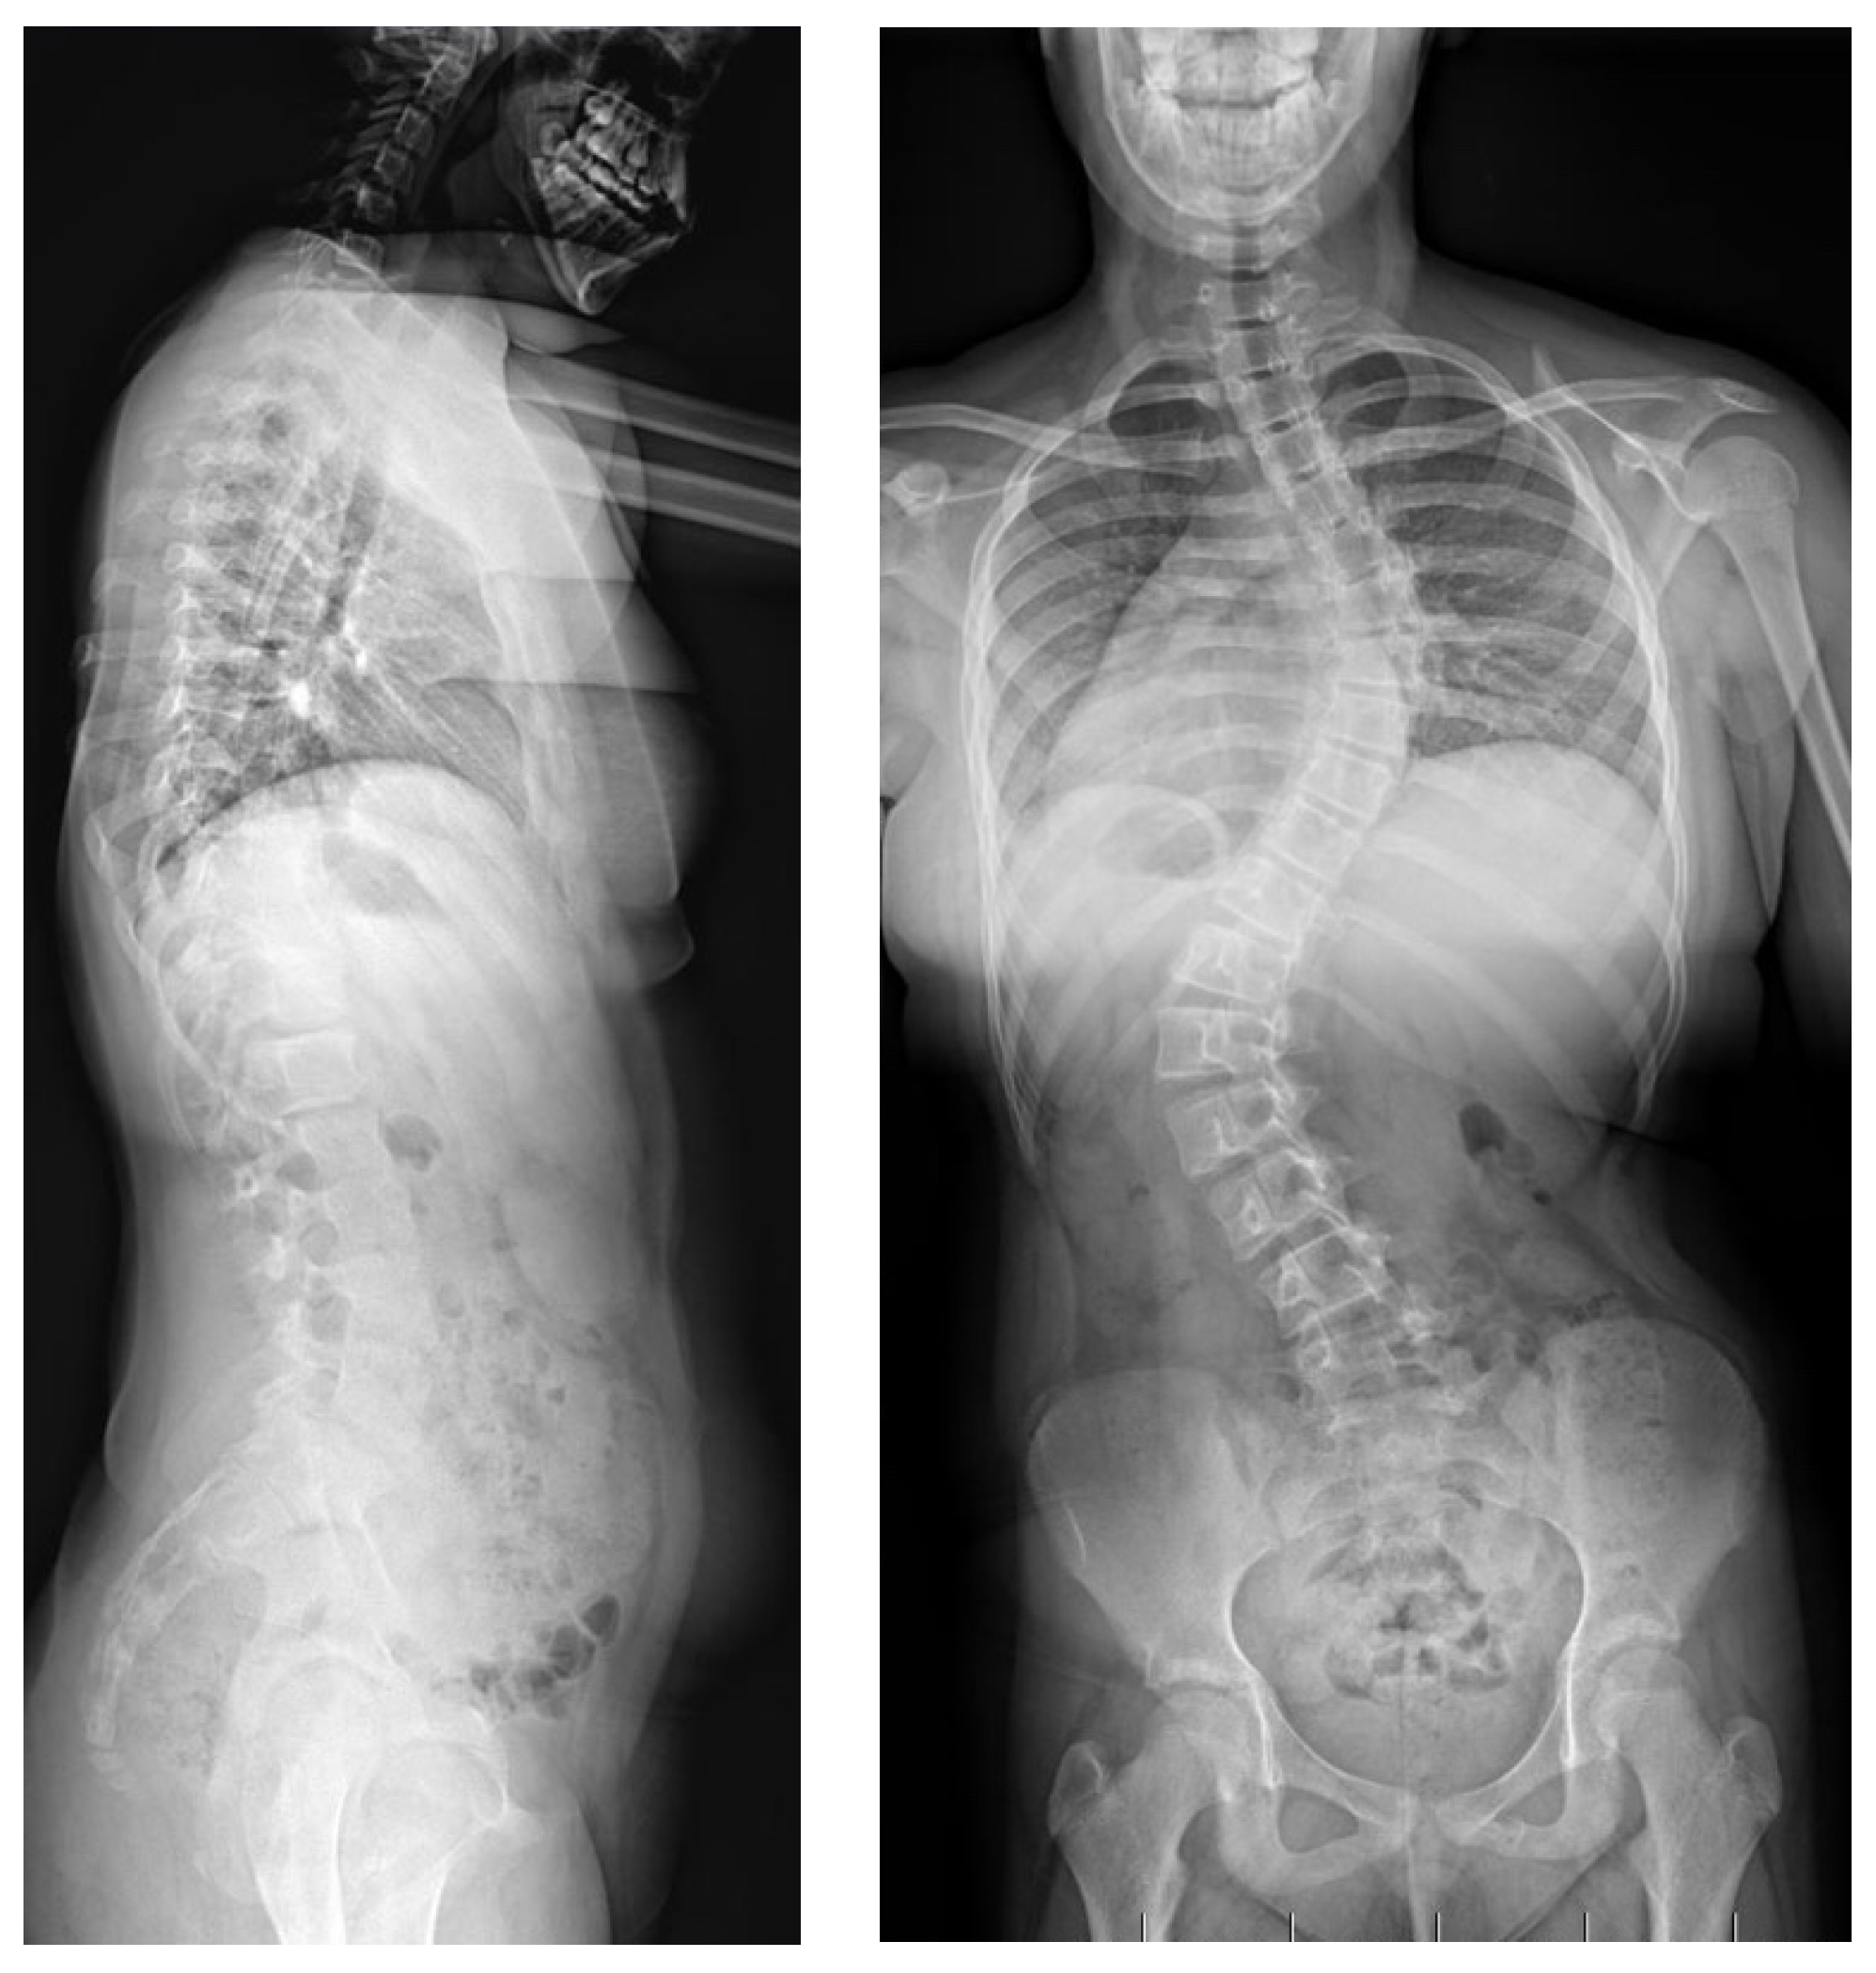

2.2. Example of Early-Onset Idiopathic Scoliosis